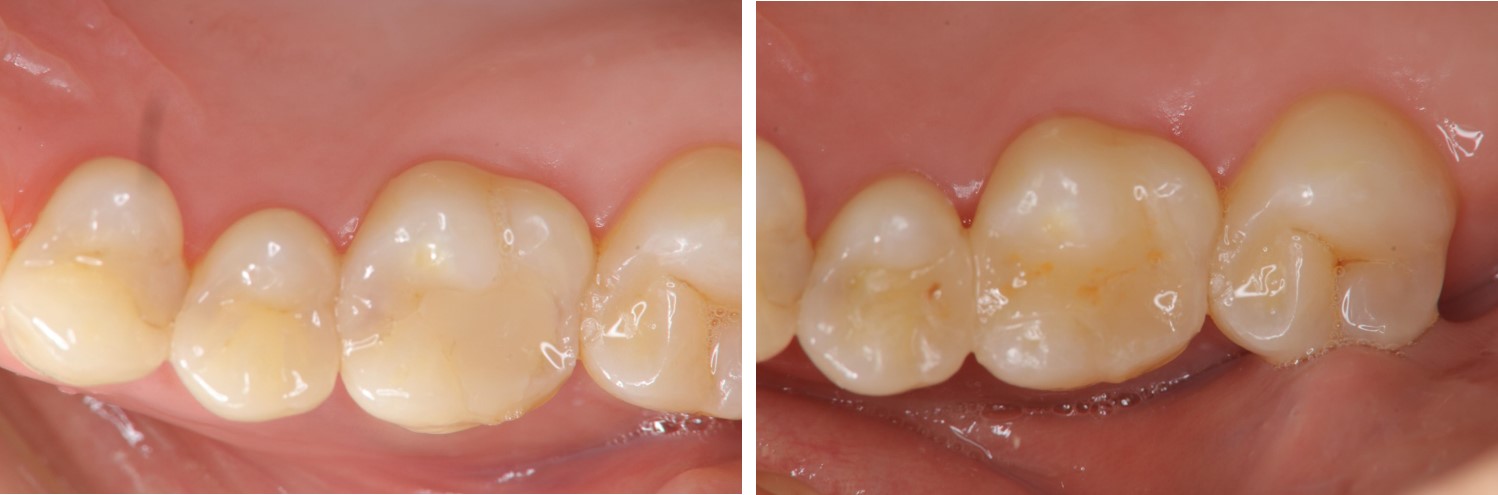

術前、術後比較

當蛀牙破壞程度大,陶瓷崁體是根據蛀牙的窩洞量身訂做,不管是顏色、精密度都是最佳的選擇,因此是非常美觀與持久的填補窩洞材料與技術。